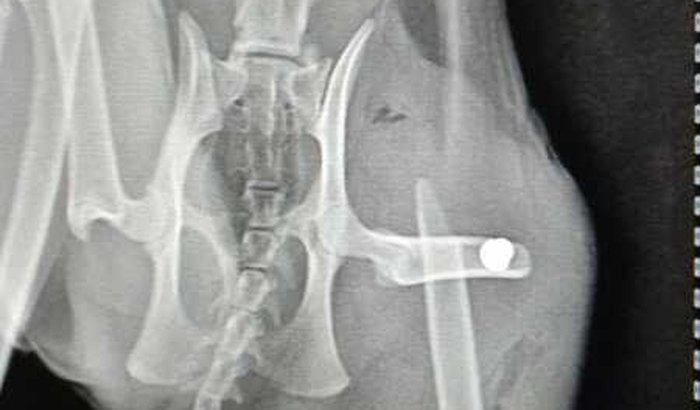

Meu nome é Nathália e tenho 11 animais resgatados/adotados. Dia 16/06/2022 uma das minhas gatas levou um tiro no fêmur a curta distância pátio de casa, não conseguimos ver o agressor e foi registrado boletim de ocorrência. Estou pedindo ajuda para conseguir arcar com os custos de todo tratamento. Ela realizou exames, teve que passar por cirugia para colocação de placa e reconstrução muscular. Sempre ajudei animais de rua e arco com os custos dos meus adotados, dessa vez peço ajuda, o total deu em torno de 2.800 reais e no momento não tenho condições de pagar sozinha esse valor. Obrigada.